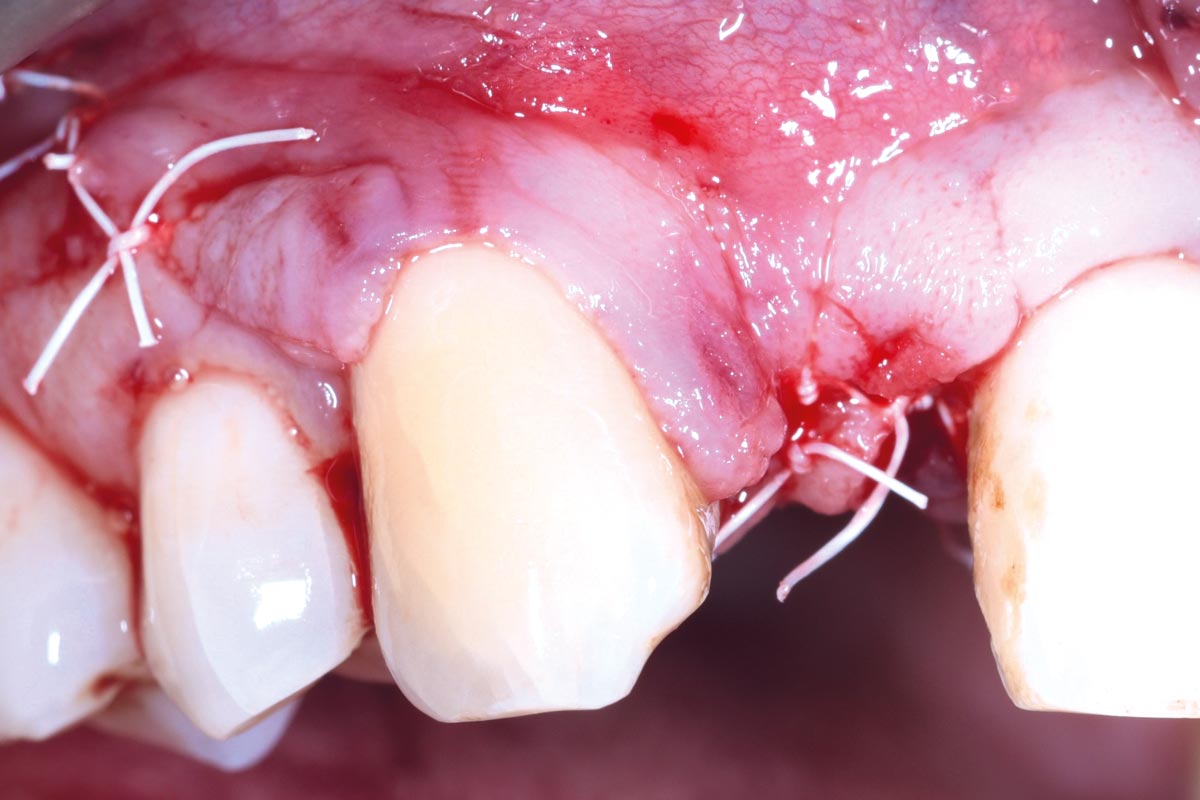

09/13 - Closure with PTFE sutures

Immediate implant placement in the maxilla with contour GBR - Dr. K. Loukas